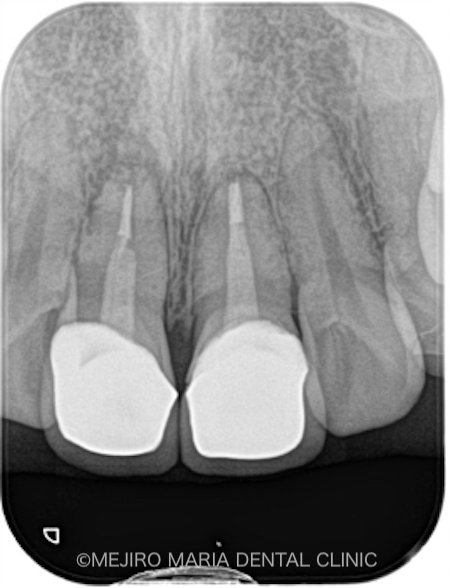

|術前レントゲン画像_治療後1-1.png)

|術直後レントゲン画像_治療後2-1.png)

|術後レントゲン画像_治療後3.png)

術後2週間で、術野の腫脹はほぼ消えて、術前に見られていた瘻孔(フィステル)の消失も確認できました。

3ヶ月後には瘻孔(フィステル)と、術前に訴えていた違和感は消失し、術野の歯肉の治癒も良好であることを確認しました。レントゲンでも、根尖部付近の骨の再生が認められたため、予後良好と判断しています。